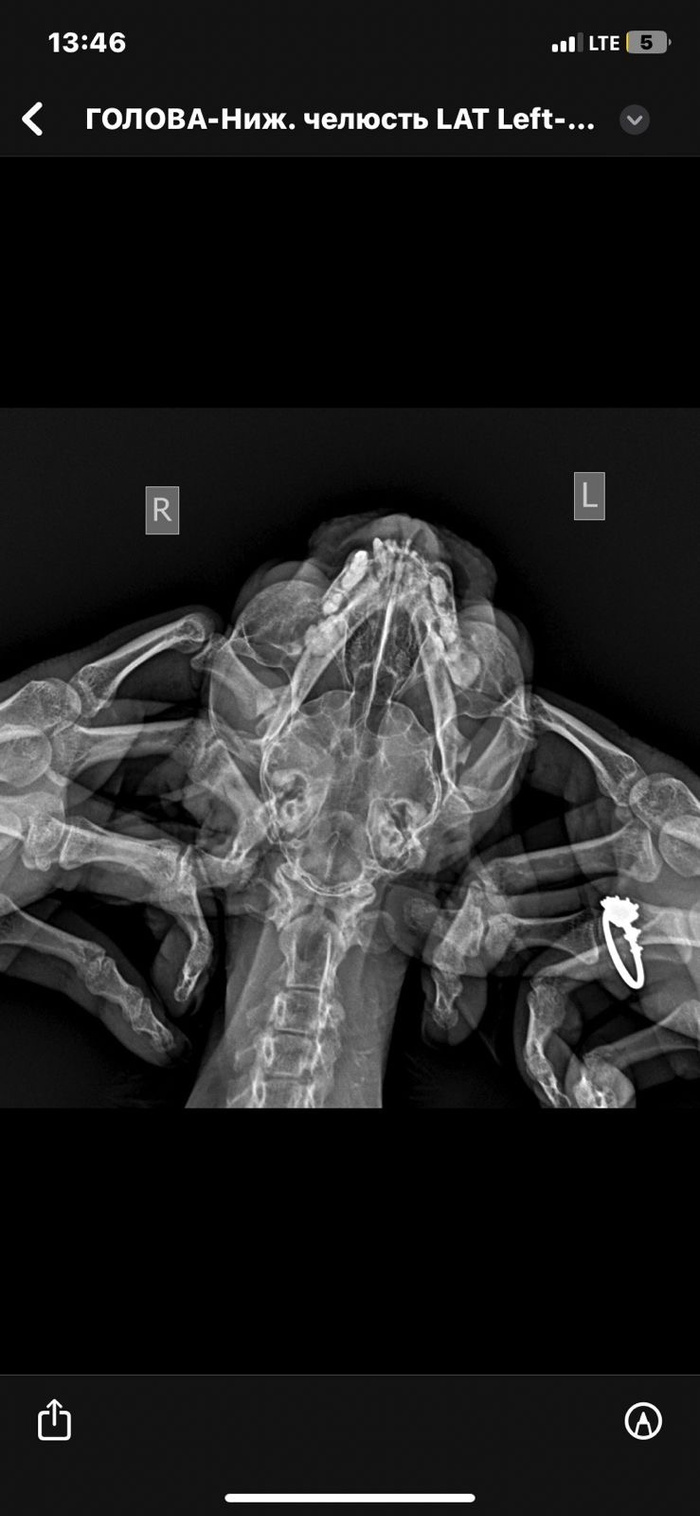

Здравствуйте, коту 18 лет, кастрирован, зубов почти нет, вес 2.7кг

Очень быстро вздулся подбородок и прорвался, оттуда сочится жидкость.

Сделали рентген, сказали ВОЗМОЖНО онкология, послали на кт под наркозом, мы соответственно не сделали из-за возраста.